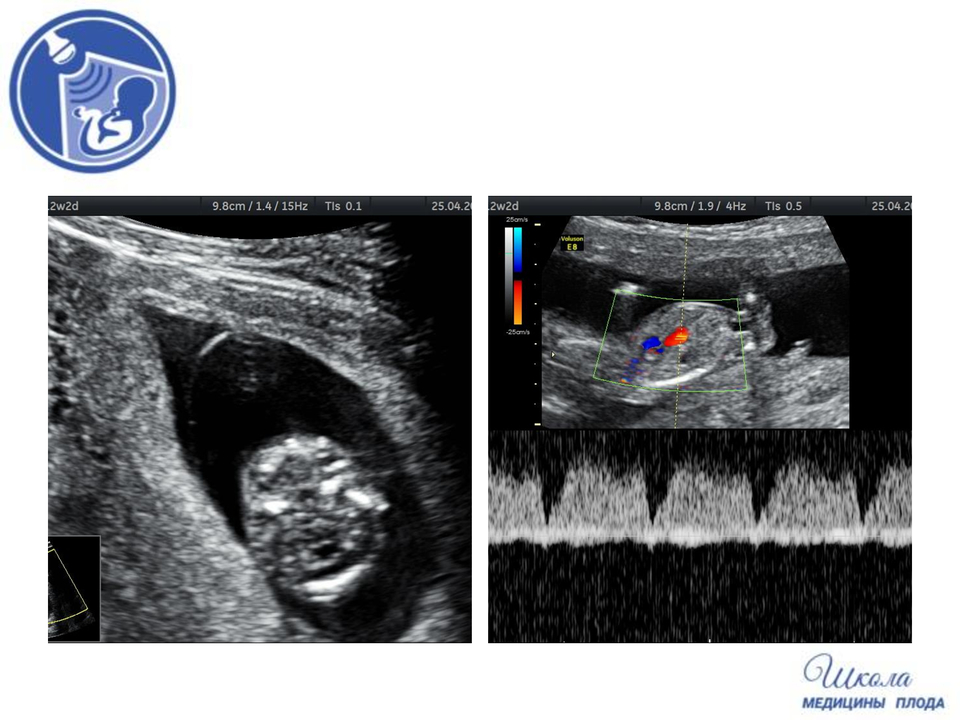

- Так же у этого плода был выявлен порок сердца – атрезия митрального клапана и гипоплазия аорты. В 4камерном срезе видно отсутствие тока крови через митральный клапан, в то время, как трикуспидальный клапан работает.

- В срезе через 3 сосуда видно, что поток крови в аорте меньше, чем поток в легочном стволе